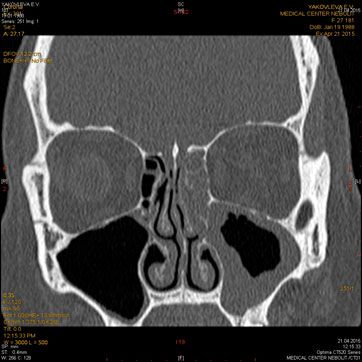

МСКТ придаточных пазух носа, лицевого черепа, орбит

Показания:

- подозрение на опухоль, кисту

- воспалительные заболевания при отсутствии эффекта от бактериальной терапии

- травма

- аномалии развития

Подготовка: не требуется.

Предварительное рекомендуемое обследование: заключение оториноларинголога